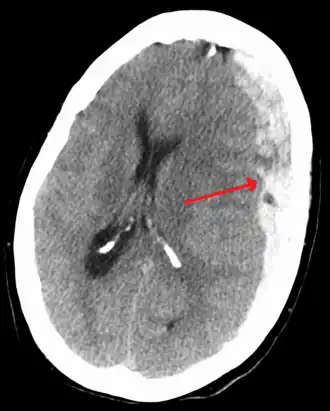

| Субдуральная гематома (обозначена стрелкой) со значительным смещением срединных структур. | |

При компьютерной томографии субдуральные гематомы имеют классическую серповидную форму, однако, могут выглядеть и линзовидно, особенно в начале кровотечения; это может вызвать затруднения в дифференциальной диагностике субдуральной и эпидуральной гематом. Более достоверным признаком субдуральной гематомы является её относительно большая распространённость по ходу полушария головного мозга с преодолением швов черепа, в отличие от эпидуральной гематомы. Субдуральная гематома также может выглядеть как «наслоение» повышенной плотности по ходу намёта мозжечка; такая гематома может быть хронической и стабильной, и косвенными минимальными признаками кровоизлияния могут служить сглаженность прилегающих борозд и медиальное смещение границы между серым и белым веществом.